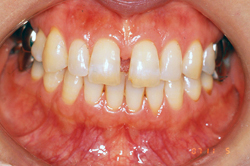

症例1 ・・・禁煙後レーザー治療を行いました。後にホワイトニングを含めた審美治療を行います。

「オペレーザー03S2」という炭酸ガスレーザー機器による最先端の歯科治療を導入しております。今までの「歯医者は痛い」のイメージをくつがえす安全かつ痛みの少ない画期的な治療が可能となりました。

レーザー治療なら多くの場合は麻酔が必要なく、出血もほとんどなく傷あとも残りにくい他、治りも早く、治療後の痛みもほとんどありません。